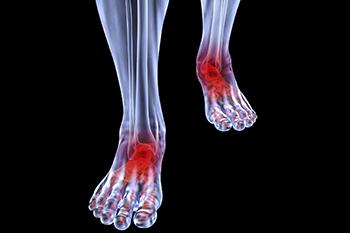

Arthritic Foot & Ankle Care

Conditions affecting the feet due to complications with arthritis can take many forms, including osteoarthritis, rheumatoid arthritis, gout, psoriatic arthritis, and ankylosing spondylitis. Osteoarthritis typically affects the joint connecting your big toe to your...